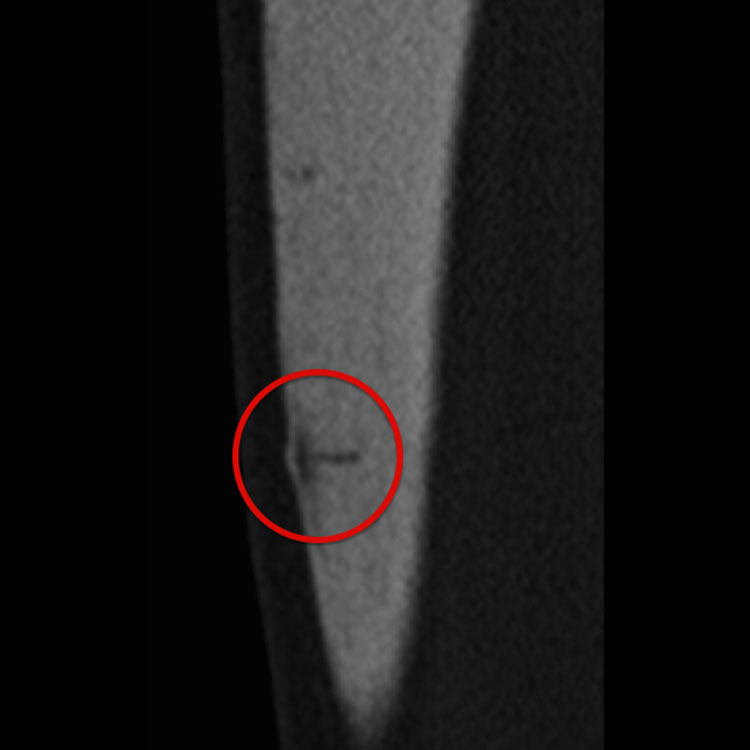

전방 경골 (Anterior tibia): 진단 후 모든 고충격 활동을 최대 3개월 동안 피해야 합니다. 치유에 최대 6개월이 걸릴 수 있으며, 저강도 펄스 초음파(LIPUS)가 골 치유에 도움을 줄 수 있습니다. 외과적 치료는 골수내정 고정술 또는 전방 인장 밴드 플레이팅 등이 고려될 수 있습니다.